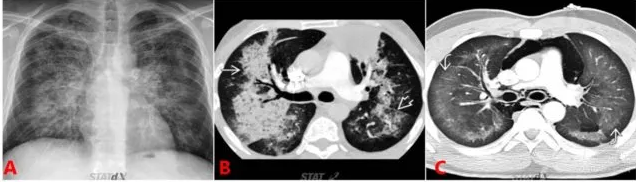

3. 小叶间隔和叶间裂增厚

QQ浏览器截图20200505212553.png

图 3  心源性肺水肿典型表现:小叶间隔

先简单介绍一下「肺小叶」。

影像学上所说的肺小叶是多指次级肺小叶(图 3A),是肺结构的最小独立单位,以结缔组织间隔为边缘,由小的小叶细支气管和肺动脉支配,是解释 HRCT 表现的关键解剖结构。图 3B1 中白箭所指即为小叶间隔。

QQ浏览器截图20200505212628.png

图 4  心源性肺水肿典型表现:小叶间隔增厚

心衰发生后,由于构成小叶间隔的间隔静脉和淋巴管回流不畅,小叶间隔厚度增加(对比同一层面,图 3B2 中的小叶间隔明显增厚),这也就是胸片 kerleyB 线的形成原理(图 4A)。图 4B/C/D 所示即是 CT 图像上心衰引起的小叶间隔增厚的典型征象。

同理,心衰发生后,患者的 CT 表现上也??沙鱿中啬ひ都淞训脑龊窈湍:?/span>(图 5)。

QQ浏览器截图20200505212702.png

图 5 心源性肺水肿典型表现:胸膜叶间裂的增厚和模糊

图 5A、B、C 均为心力衰竭患者的胸部 CT 显像,均可见叶间裂明显增粗、模糊。